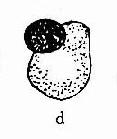

(四)精子形态(见图11-1)

1.正常精子形态检测政党精子形态的应遵循严格标准:①正常精子头部呈椭圆形,其正常标准为头部长度为4.0-5.5μm,宽为2.5-3.0μm,长与宽的比值为1.5-1.75项体区占头部的40-70%;②必须不存在颈、中段或尾部的缺陷;③细胞质微粒不大于正常头部的1/3;④将所的处于边沿异常状态的清子均列为不正常。

2.有缺陷精子:用这种形态学分析方法考虑的精子细胞功能部位,因此认为没有必要常规的去区分所有头部大小和形态之间可划或尾部缺陷之间的变异如果大多数精子细胞中出现某一种部位的异常,则应对这一普通的缺陷给予注释。需记录的缺陷有:

(1)头部形状、大小缺陷:包括大头、小头、锥形头、梨头、无定形头、空泡样头(头部大于20%区域出现不着色的空泡区、)双头或以上缺陷的联合体。

(2)颈、中段缺陷:包括缺尾可见到游离或脱落的头部,未附着或弯曲尾尾与头部长轴结呈90度角,肿胀、不规则、弯曲的中段,异常薄的中段无线粒体鞘或以上任何类型缺陷的联合体。

(3)尾部异常:包括短尾、多尾、发夹状尾、断尾、宽度不规则或卷尾、或尾部伴有末端微滴,或以上任何类型缺陷的联合体。

(4)细胞质微粒:大于正常头部的面积的1/3。细胞质微粒一般位于颈可中段部分,也有未成熟精子微粒沿尾部分而布在不同部位。

许多形态学的异常的精子有多种缺陷。当多种缺陷同时存在时,只记录一种,但应优先记录头部缺陷,其次为中段缺陷,最后为尾部缺陷。每种精子缺陷的平均数目称为畸形精子指数,是预测精子在体内、体外功能有意义的指标,因此形态学分析应该是多参数原,应分别记录每种缺陷。异常形态见图11-1。

图11-1 精子形态

[临床意义] 正常精液中正常形态的精子应≥30%,精液中正常形态的精子减少称畸形精子症,与睾丸、附睾的功能异常密切相关。可见于生殖系感染。精南疆静脉曲张、雄性激素水平异常时;某些化学药物(如硝基唪喃妥英)、遗传因素也可影响睾丸生精功能,导致畸形精子增多。